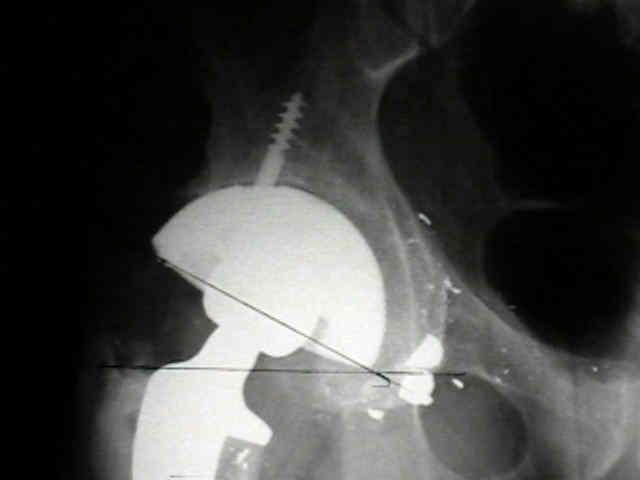

- postoperative films, however, indicate that the cup was lateralized (hence, reaming was inadequate);

- in retrospect, the radiographs which are rotated externally (like an iliac oblique) tend to falsely minimize the necessary amount of medialization where as X-rays which are rotated internally (like an obturator oblique), tend to over-estimate the necessary amount of medialization